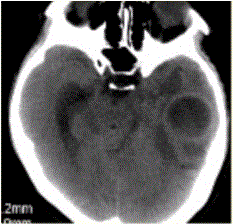

问题 患者女,26岁,头痛、低热10d余,既往有左侧慢性中耳炎病史。CT表现如下图。 初步诊断为

选项 A.脑脓肿 B.胶质瘤 C.脑血肿 D.脑梗死 E.脑囊虫

答案 A